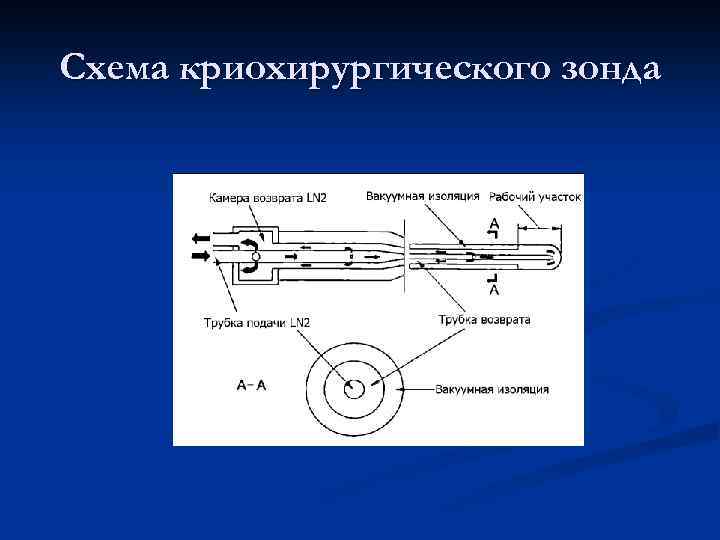

Схема криохирургического зонда

Схема криохирургического зонда